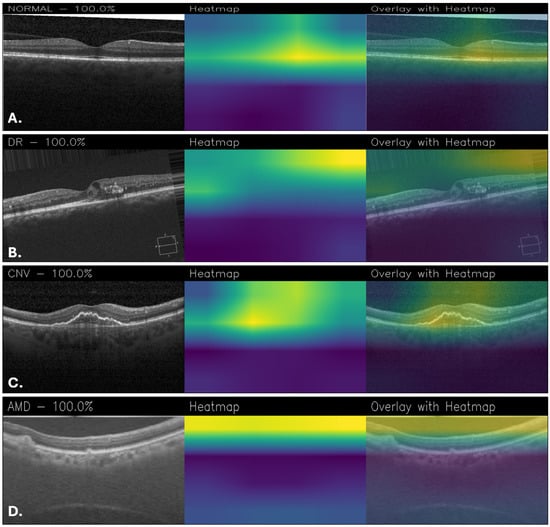

The explainability is critical to understand which areas of the images are used for classification, so activation maps were generated with Grad-CAM. According to them, NeoNet focuses attention on specific and relevant regions of retinal images, suggesting a good ability to learn discriminative patterns. However, for example, the Grad-CAM maps of CUSTOM_CNN are more accurate and detailed, showing better localization of salient features than NeoNet. This aspect suggests that despite the higher overall accuracy of NeoNet, CUSTOM_CNN may offer greater transparency in decision making, a crucial factor in medical fields. Figure 10 shows a series of classification examples made through the use of the NeoNet model. For each of the four retinal conditions (NORMAL, DR, CNV, and AMD), the following cases are shown: the original image (left), the heatmap of model activations (middle), and the overlay of the heatmap on the image (right). The highlighted regions indicate the areas that most influenced the classification.

Figure 10. Grad-CAM visualizations obtained with NeoNet for healthy retina (A), DR (B), CNV (C), and AMD (D).

In the Grad-CAM overlays, the normal case (Figure 10A) shows concentrated activation at the foveal pit and adjacent retinal layers. For DR (Figure 10B), attention is directed toward the superior retinal boundary and areas with localized structural abnormalities. In CNV (Figure 10C), the model emphasizes the central lesion and surrounding retinal thickening. For AMD (Figure 10D), activation is distributed along the retinal pigment epithelium and subretinal regions, highlighting drusen-like changes.